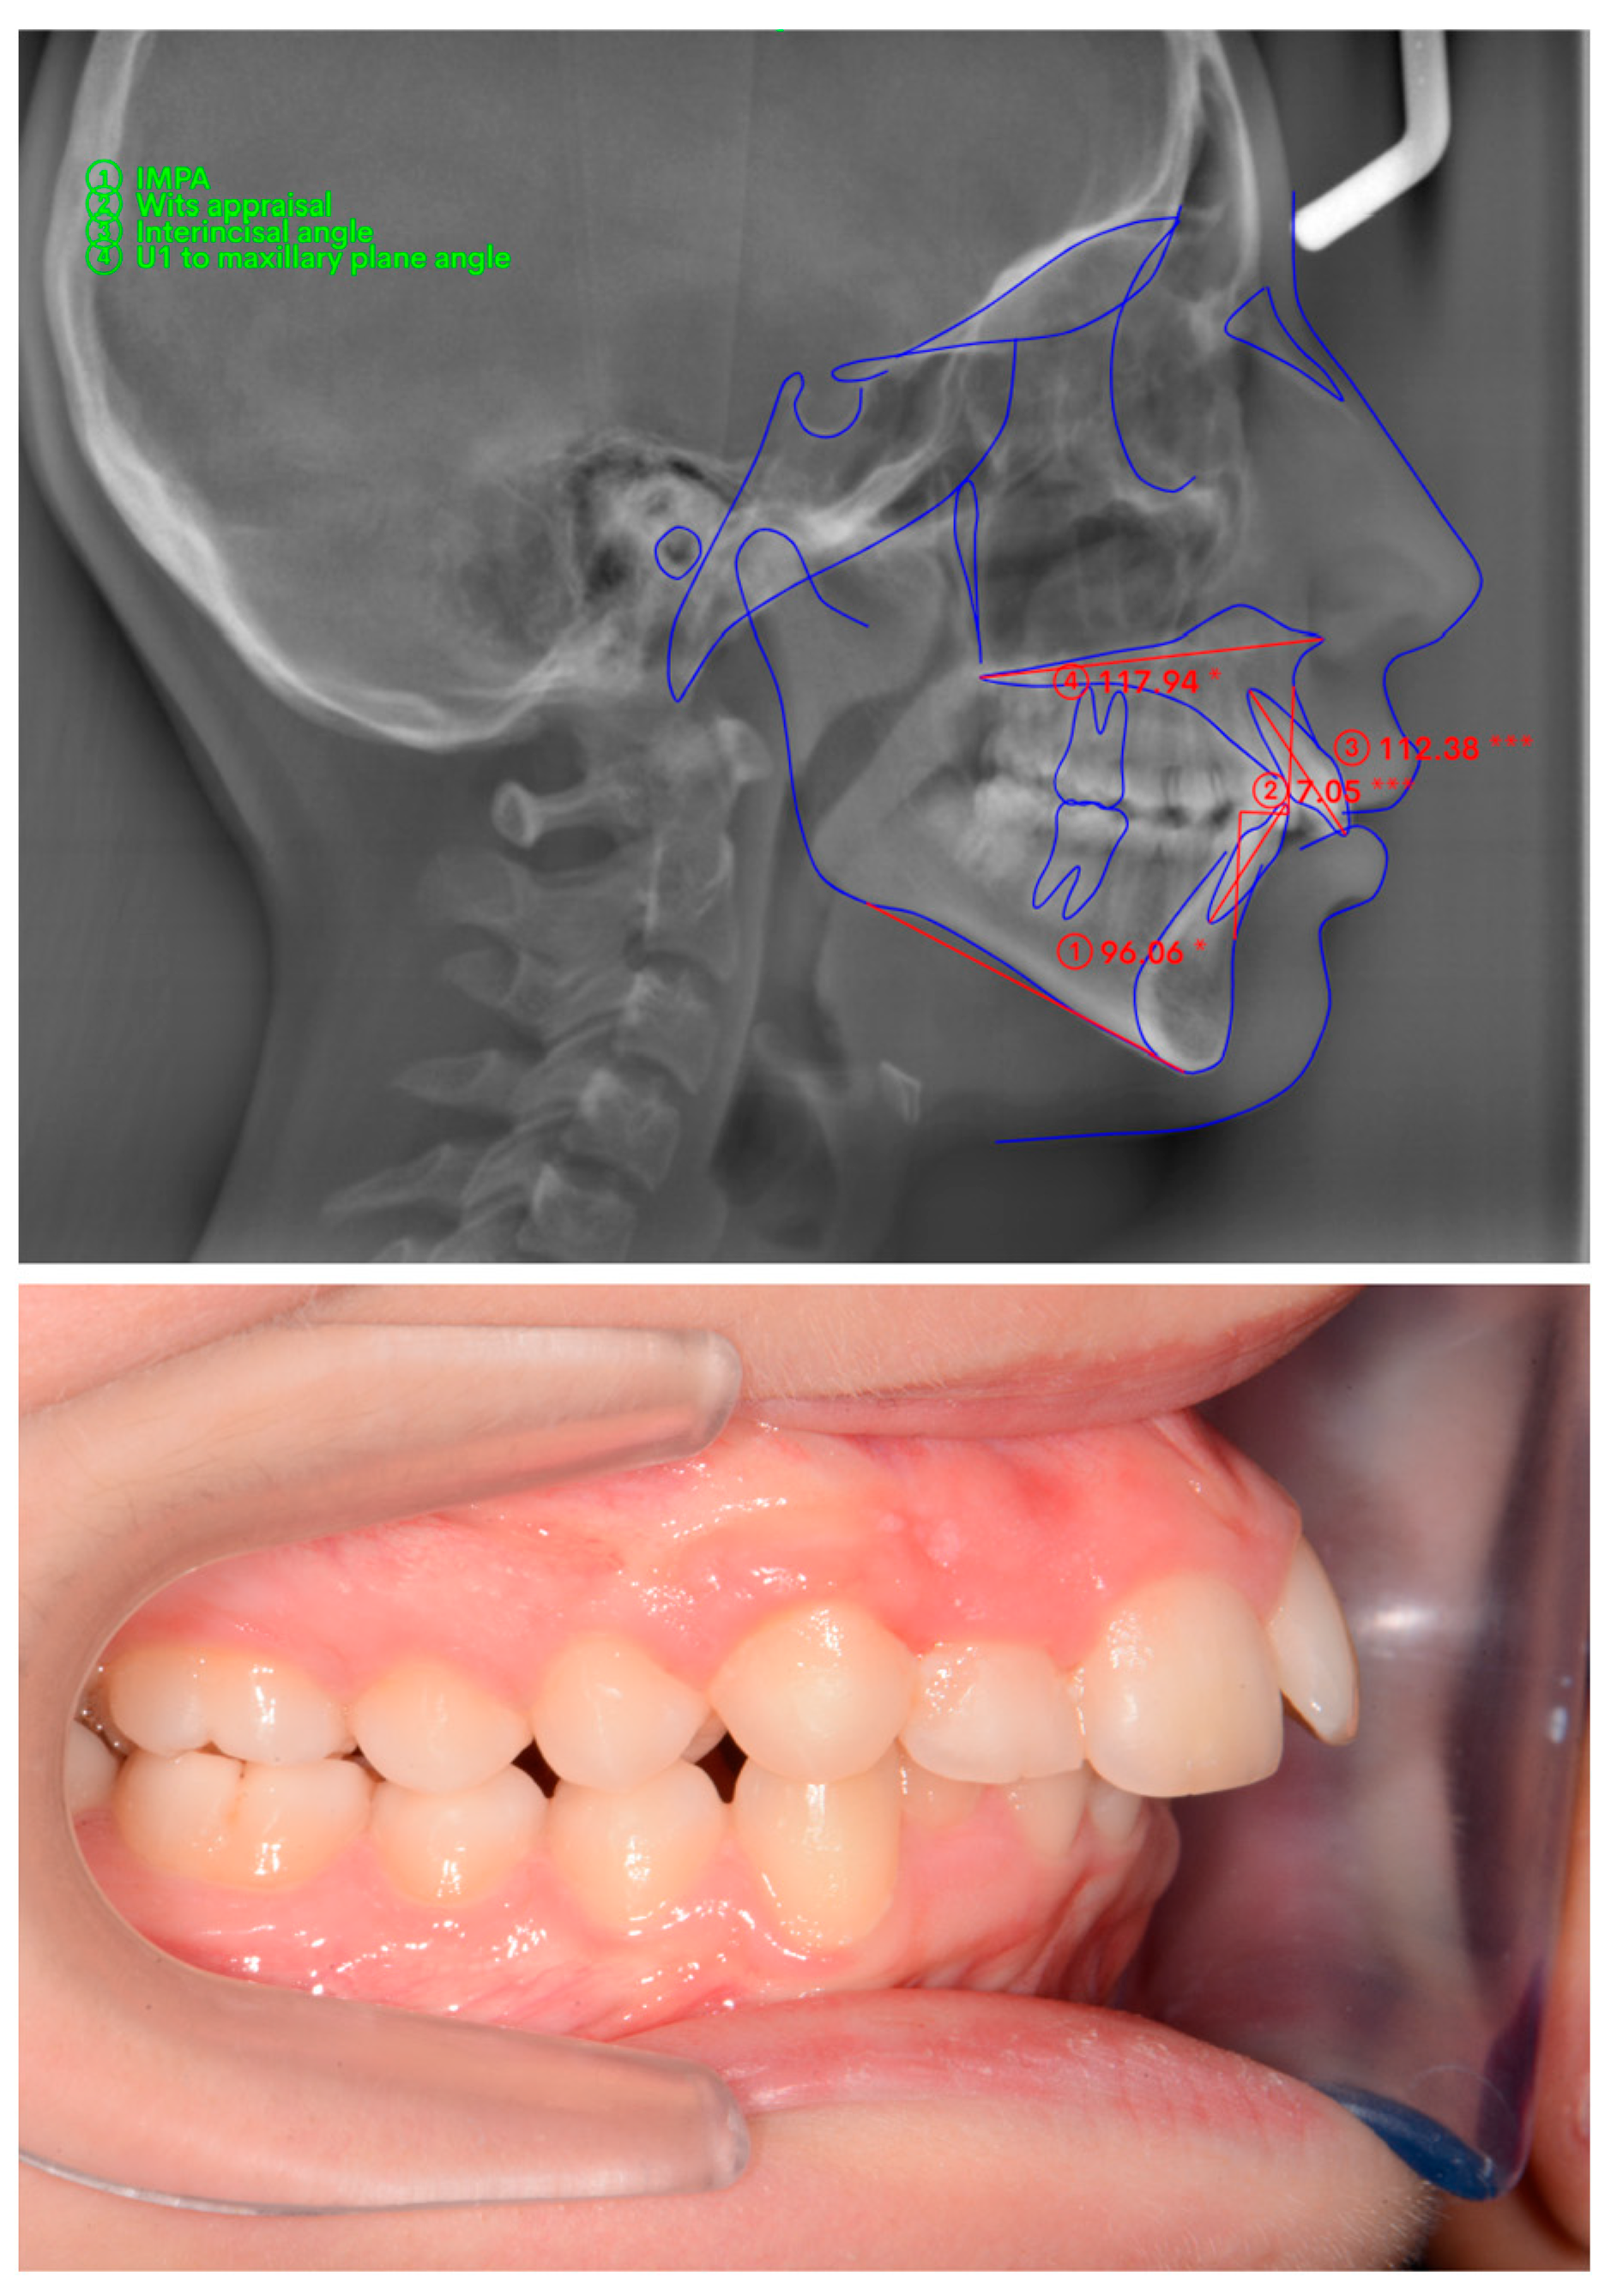

The A point, B point, Anterior Nasal Spine, Posterior Nasal Spine, Gonion, Menton, U1, and L1 were marked (Figure 1) and four measurements were made (Figure 2) on lateral cephalometric radiographs.

Figure 2. Cephalometric measurements on WebCeph and intraoral photographs. (Performed cephalometric measurements are demonstrated on the actual screenshot of WebCephTM digital cephalometric measurement program (AssembleCircle Corp., Hwaseong-si, Republic of Korea) interface. The “*” and “***” are automatically generated markers in order to point to the deviation of the measurement from norm values).